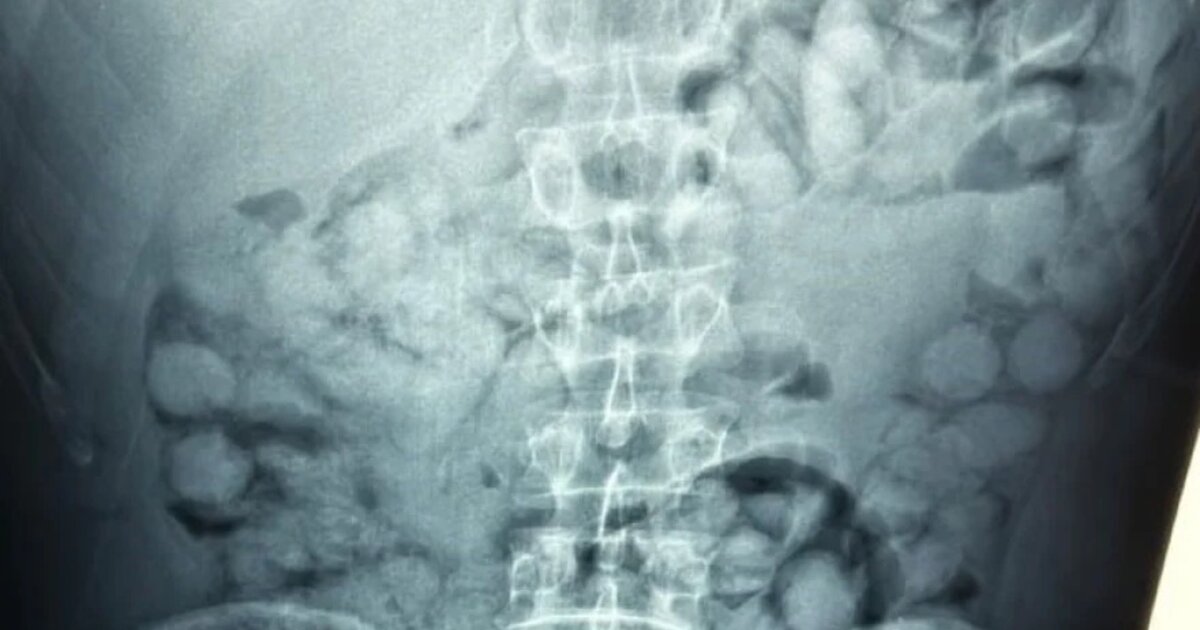

Ένας άνδρας, από τη Βραζιλία, συνελήφθη σήμερα το πρωί στο αεροδρόμιο «Ελ. Βενιζέλος», κατηγορούμενος ότι είχε καταπιεί σημαντική ποσότητα κοκαΐνης.

Σύμφωνα με την ΕΛΑΣ, ο άνδρας έφτασε στην Αθήνα, μέσω Παρισιού και στον έλεγχο που διενεργήθηκε, διαπιστώθηκε ότι είχε καταπιεί περίπου 100 συσκευασίες κοκαΐνης.